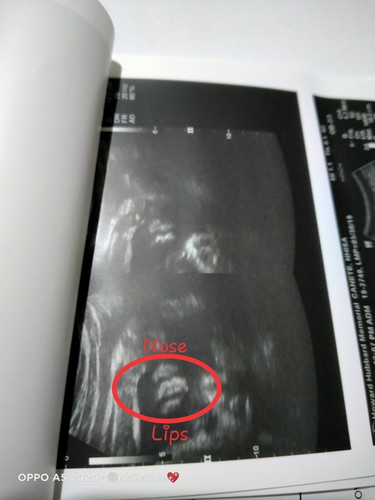

Mas maliit sya sa AOG nya

29 weeks via UTZ ang size nya. Maliit sa supposed to be na 31 weeks lang. Is it okay? Tapos mga sis medyo nag open cervix ko and ang length ng cerbix ko is 4cm @31 weeks. May spotting rin ako noong nakaraang araw kumokonti until now parang tulo nlng na brown. Any tips mga sis? Cord coil rin si baby :( Niresetahan ako mg progesterone (heragest) ni OB, nainjectan na rim ng dexa twice and total bedrest until Feb. 6. Sana makayanan namin ni bany umabot sa maturity nya huhu